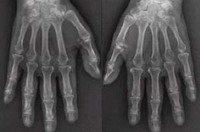

SANITA’, Artrite reumatoide: un progetto di legge per il diritto alla cura |